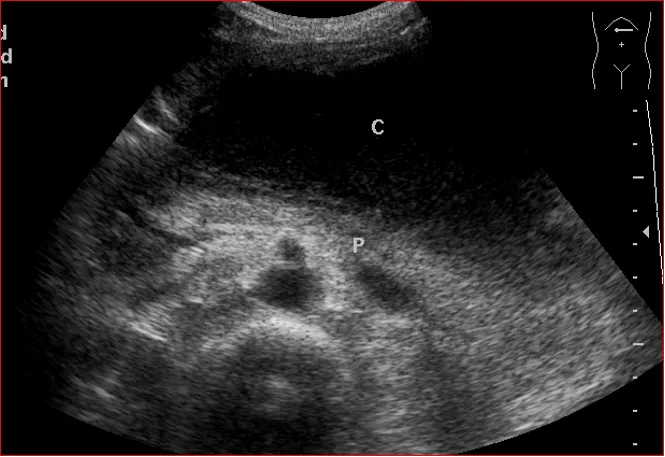

上腹部横切显示胰体部占位与腹腔干的关系

● 灰阶超声表现

1.直接征象

①小于2cm的肿瘤多为均匀低回声,圆形,与正常组织无明显界限,无包膜,后方回声衰减不明显

②随肿瘤增大肿块内回声不均匀,部分可有钙化、液化、或呈高回声改变,肿物边界不清,呈浸润性生长,形态不规则,后方回声衰减

②肿瘤附近的血管被推移、挤压、变形或被肿瘤包绕